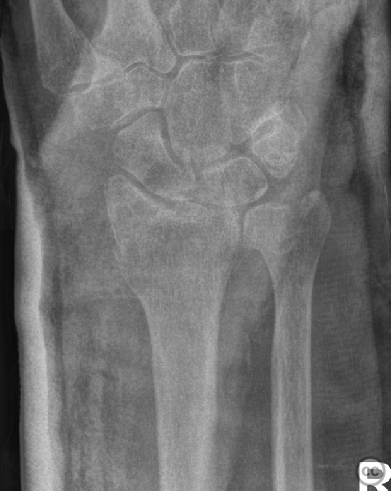

Clinical and radiological findings:  A 72-year-old female sustained a multifragmentary, dorsally displaced distal radius fracture after a fall down stairs. Initial reduction revealed a 180-degree flipped fragment of the volar ulnar articular margin, unreducible by closed means. There was no mention of associated neurovascular compromise or open injury. Radiographs and intraoperative fluoroscopy confirmed the presence of a multifragmentary intra-articular fracture (AO/OTA 23-C3), with a flipped volar ulnar fragment and radial styloid impaction. The distal radioulnar joint alignment was restored postoperatively.

Planning remarks:  The preoperative plan was for open reduction and internal fixation via an Extended (eFCR) volar approach, with specific attention to direct visualization and reduction of the flipped volar ulnar articular fragment, anatomical reduction of the radial styloid, and fragment-specific fixation using mini-fragment plates and provisional Kirschner wires.